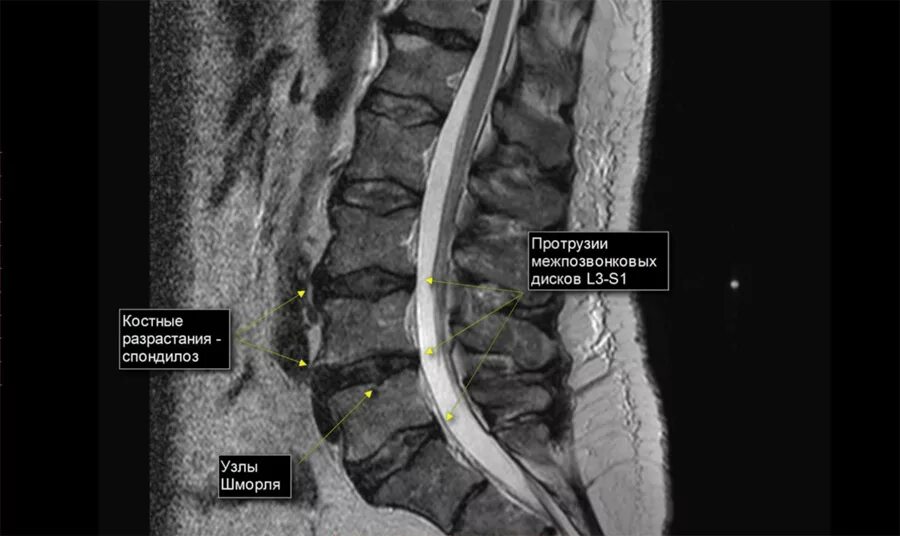

Дорзальная протрузия диска что это такое